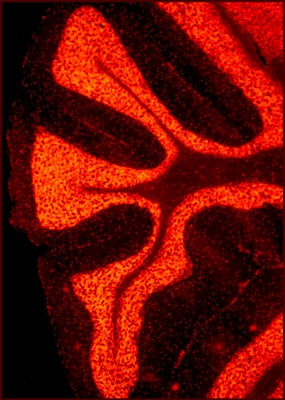

This is a section of a mouse cerebellum (from the Latin “little

brain”). Located

at the lower back of the brain, the cerebellum receives and

sends information

to other organs. Accordingly, this information processing center

contains more

than 50 percent of the total neurons in the brain. To

accommodate such a large

number of cells into such a small space, the outer region of the

cerebellum is

thrown into folds, or lobules. In this photomicrograph, every

red dot indicates

one single cell that is undergoing cell division. Conditions

such as schizophrenia,

autism, mood disorders, dementia, and attention deficit

hyperactivity disorder

(ADHD) are all thought to be disorders of cerebellar function.